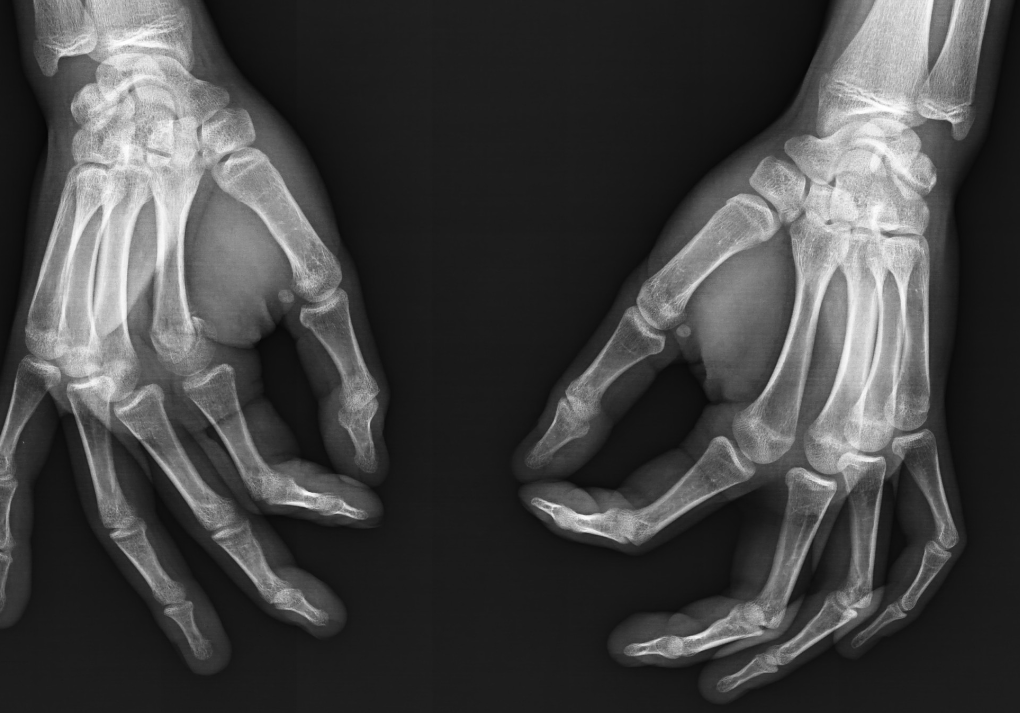

A growth plate (or an Epiphyseal plate) is a region of cartilage near the ends of long bones in children and adolescents where new bone tissue is created, causing the bone to grow in length and width.

This process continues until adolescence, when the growth plates harden into solid bone, a process called "closing" or “fusing”.

Male growth plates tend to fuse at around 16-19, once your plates have fused/closed, they will not grow any longer or wider.

Now, to find out if your growth plates are fused or not, we’re going to look at your wrist & knees for your height, and at your clavicles for your frame.

Above I've added 3 figures, from open ( A ) to fully fused ( C ), those are your growth plates, if theres a visible line like in B, they’re still open, but closer to fusion. ( You will typically see this in X-rays of teenagers). Whereas if you don’t see any lines at all, it means the cartilage has hardened into solid bone, ending any growth potential.

To continue with this method & estimate your own bone age, you’ll need an xray of your non dominant hand, including your wrist. We’re going to be evaluating a total of 13 bones.